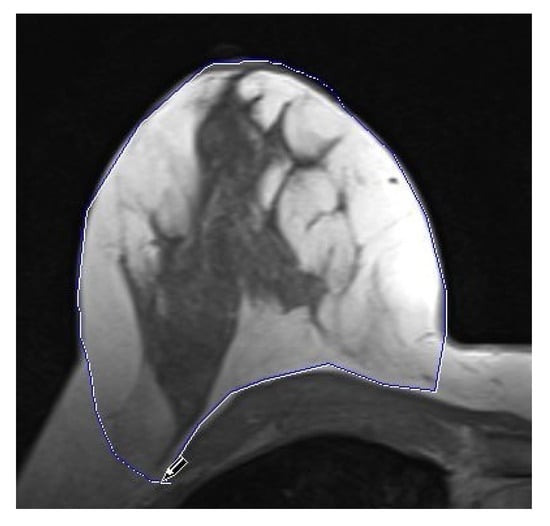

2.3. MRI Data Analysis

- Preoperative breast volume;

- Postoperative breast volume;